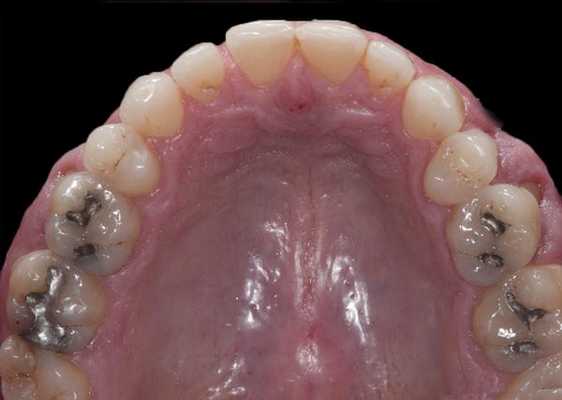

Пациент обратился за помощью с несколькими основными жалобами, главной из которых являлась эстетическая дилемма: ему не нравился цвет, размер и форма зубов (фото 1). При этом он также желал по возможности закрыть диастему между 10 и 11 зубами. Он также был обеспокоен «объемом» собственной улыбки и хотел расширить форму зубной дуги так, чтобы улыбка казалась более полной. Во время стоматологического осмотра было установлено, что пациент имел умеренную степень стирания режущих и окклюзионных поверхностей, легкую генерализированную форму рецессии с локализированной умеренной рецессией в области первых моляров верхней челюсти. Большинство боковых зубов имели амальгамные реставрации небольших и средних размеров с признаками вторичного кариеса. На 18 и 29 присутствовали металлокерамические конструкции. Все передние зубы верхней челюсти и несколько передних зубов нижней челюсти имели композитные пломбы в интерпроксимальных зонах, которые со временем изменили свой цвет.

Фото 4-7. Окклюзионный вид до реставрации, удаление прототипа, признаков кариеса и старых реставраций, заполнение поднутрений и запечатывание дентина.

Фото 15-21. Последовательность клинических процедур: вид до вмешательства, вид прототипа, удаление прототипа, дефектных амальгамных пломб и остальных реставраций, нанесение кариес-маркера, запечатывание дентина и заполнение поднутрений, установка окончательных реставраций.